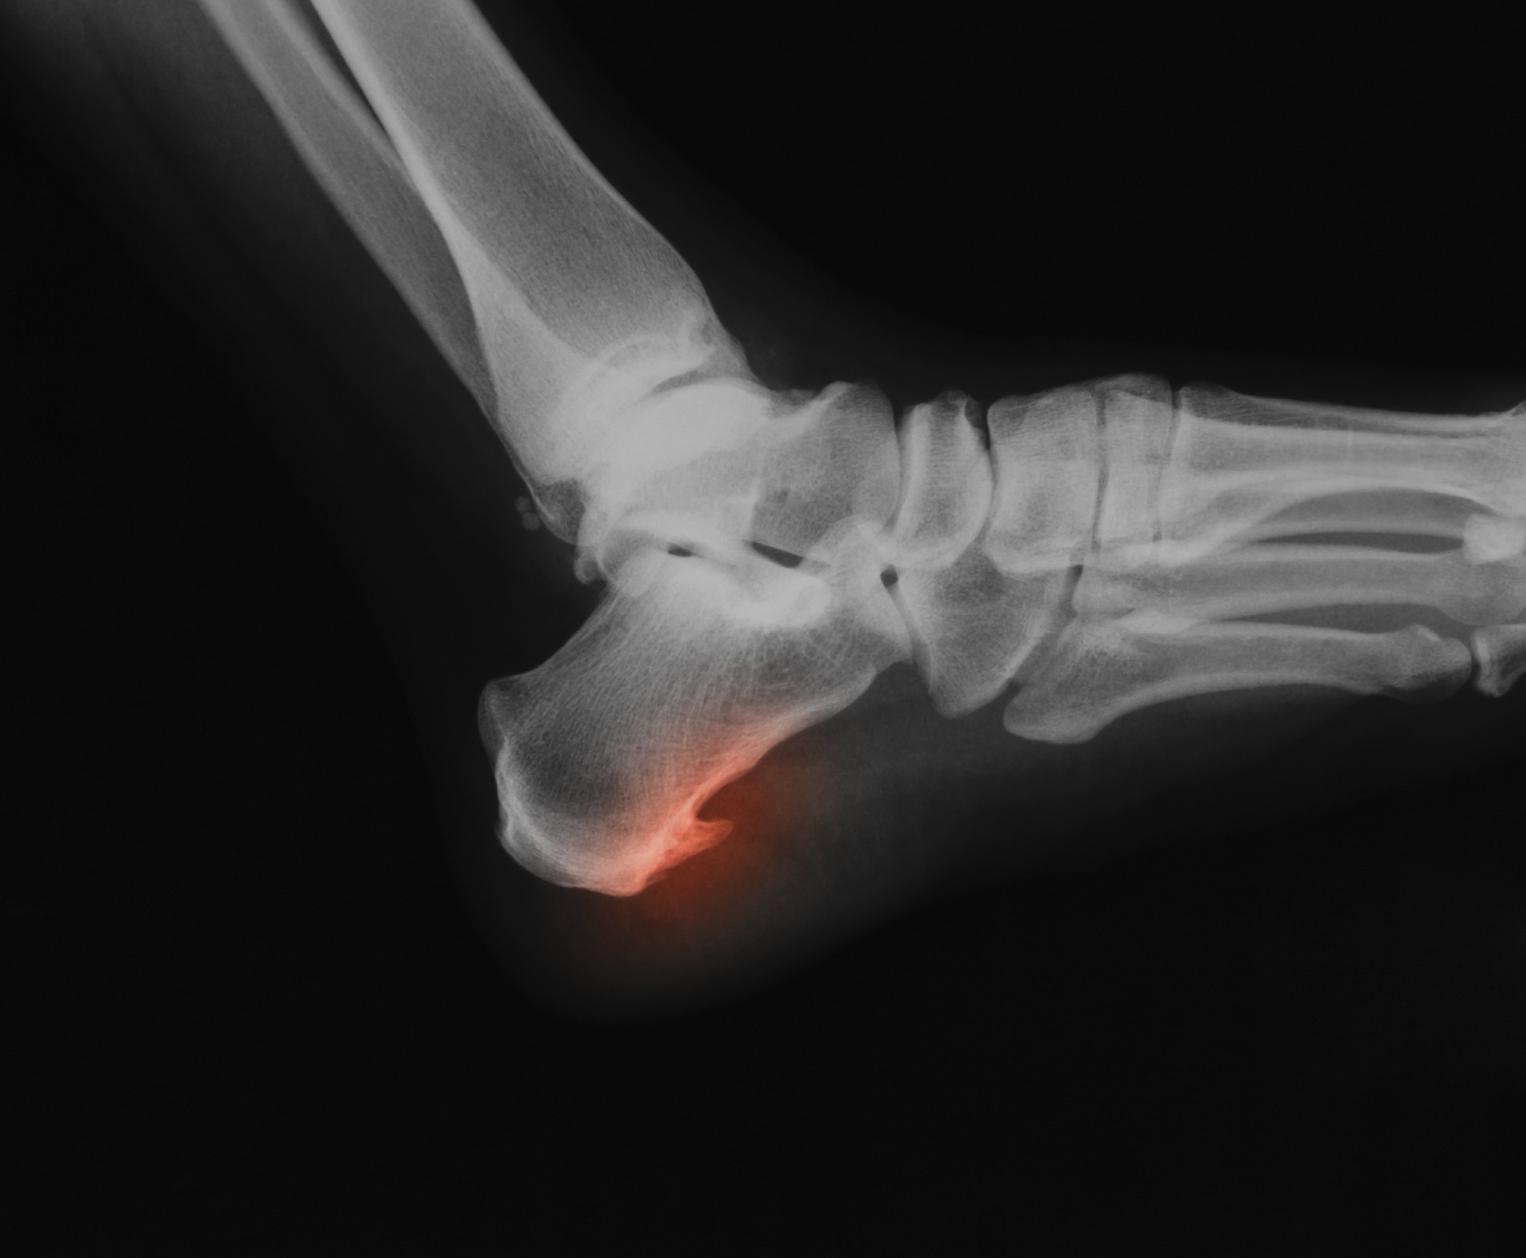

¿Te duele el talón al caminar? Puede ser espolón calcáneo

El espolón calcáneo es una protuberancia ósea al interior del hueso del talón del pie que resulta dolorosa y puede llegar a ser incapacitante para el paciente.

Para detectar su presencia, es importante acudir con el especialista en Traumatología y no automedicarse con pomadas, masajes o plantillas no especializadas ante síntomas que sugi...